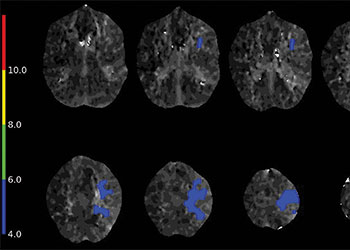

Endovascular:

Hydrocephalus and Brainstem Tumor

Author: Jonathan L. Brisman M.D., F.A.C.S., Read More!